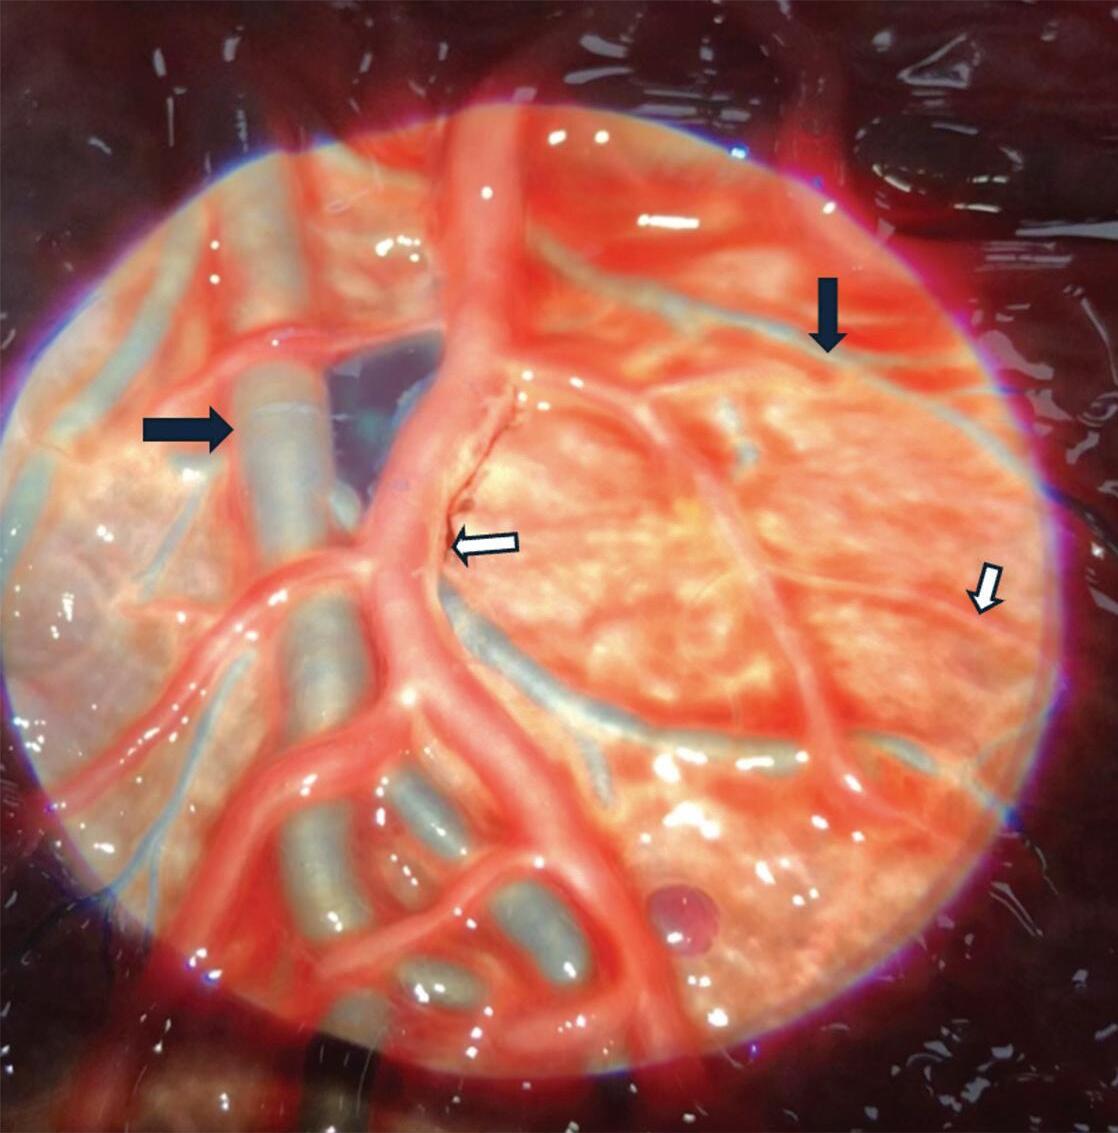

1-18. (a) RNM T2 corte sagital, (b) arteriografia digital em AP e (c) imagem intraoperatória demonstrando MAV do giro angular esquerdo com aneurisma pré-nidal (setas azuis).

Fig. 1-19. Angiografia pré-operatória em: (a) perfil em fase arterial e (b) venocapilar demonstrando uma MAV no sulco intraparietal direito grau 2, nutrida por ramo da artéria cerebral média e calosa marginal, com drenagem venosa superficial para o seio sagital superior e com aneurisma nidal (setas azuis). (c) Visão intraoperatória do aneurisma intranidal.

Fig. 1-20. RNM T1 com contraste em cortes (a) axial e (b) sagital e (c) FLAIR axial, demonstrando MAV do giro fusiforme esquerdo com presença do aneurisma pós-nidal (setas azuis). Angiografia pré-operatória em (d) AP e (e) em perfil mostrando a MAV anteriormente descrita, nutrida por ramos da artéria cerebral média e posterior esquerda, com drenagem superficial para o seio transverso e sigmoide ipsilateral e aneurisma pós-nidal venoso (setas azuis). (f) Visão intraoperatória do aneurisma pós-nidal (seta azul).